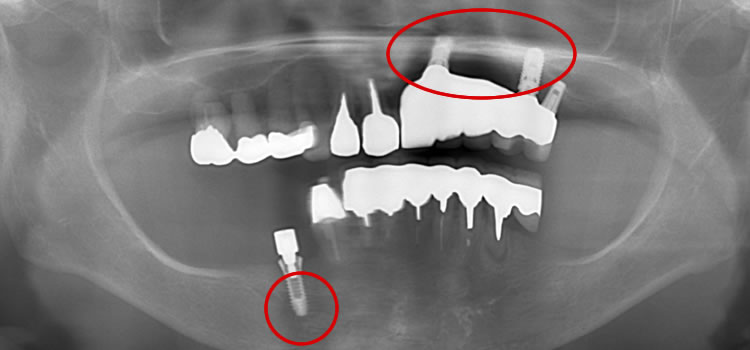

インプラント治療の相場は、30〜40万円です。 1本10万円程度の格安をアピールするインプラントには、十分注意して下さい。 下の写真は、他医院でインプラント周囲炎を起こして転院して来られた方の症例です。インプラントの埋入位置・角度ともに無計画で、それをごまかすために作られた被せ物が、見た目にも極めて不自然です。この状態からリカバリーするには、インプラントを撤去した上で、失った骨を再生をさせるなど、多くの時間と費用がかかってしまいます。